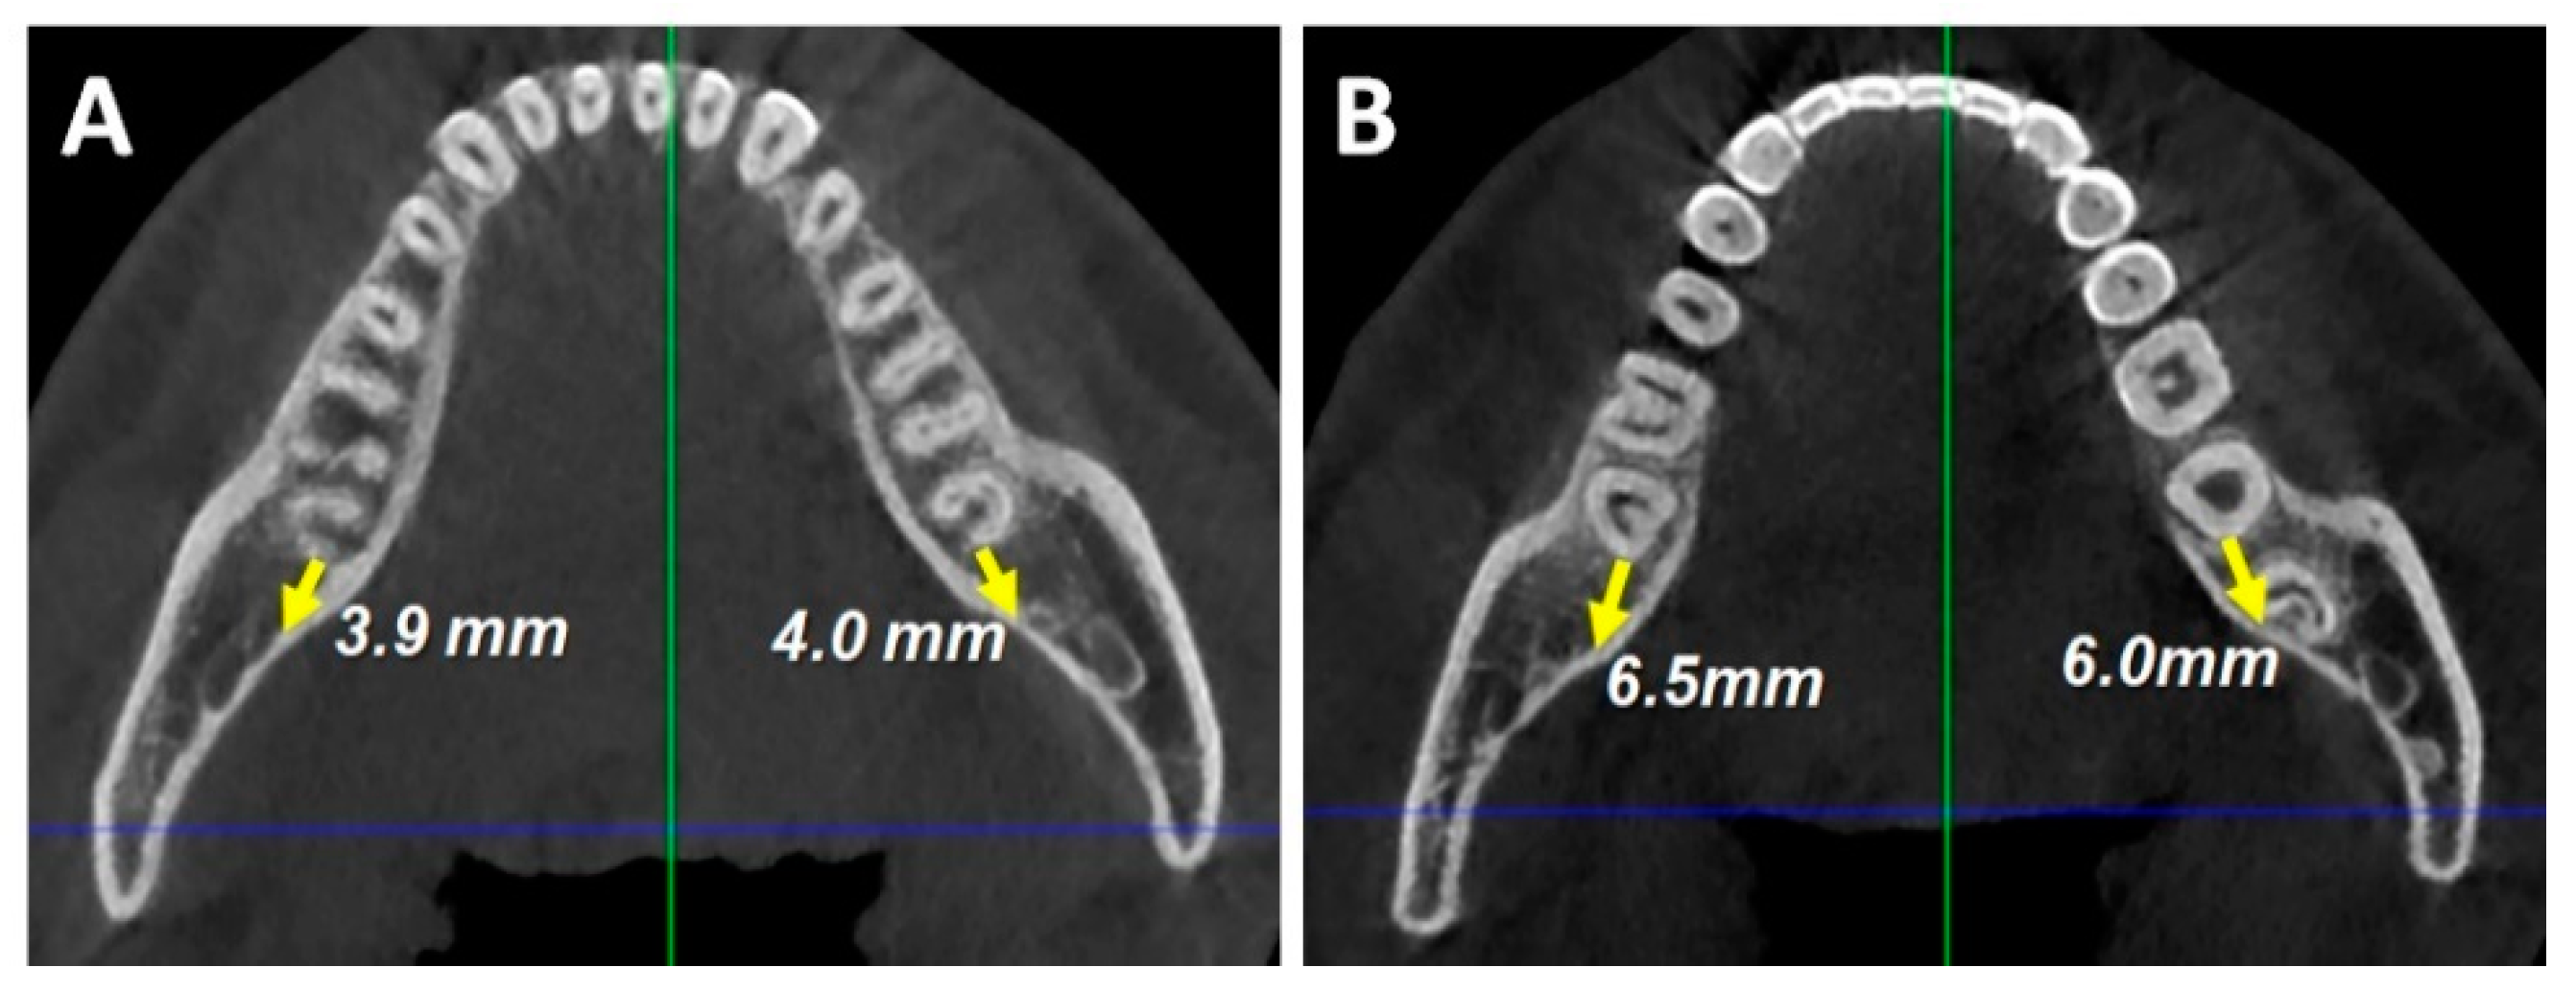

2. Case Report

2.1. Diagnosis and Etiology

2.3. Treatment Plan

2.4. Treatment Progress